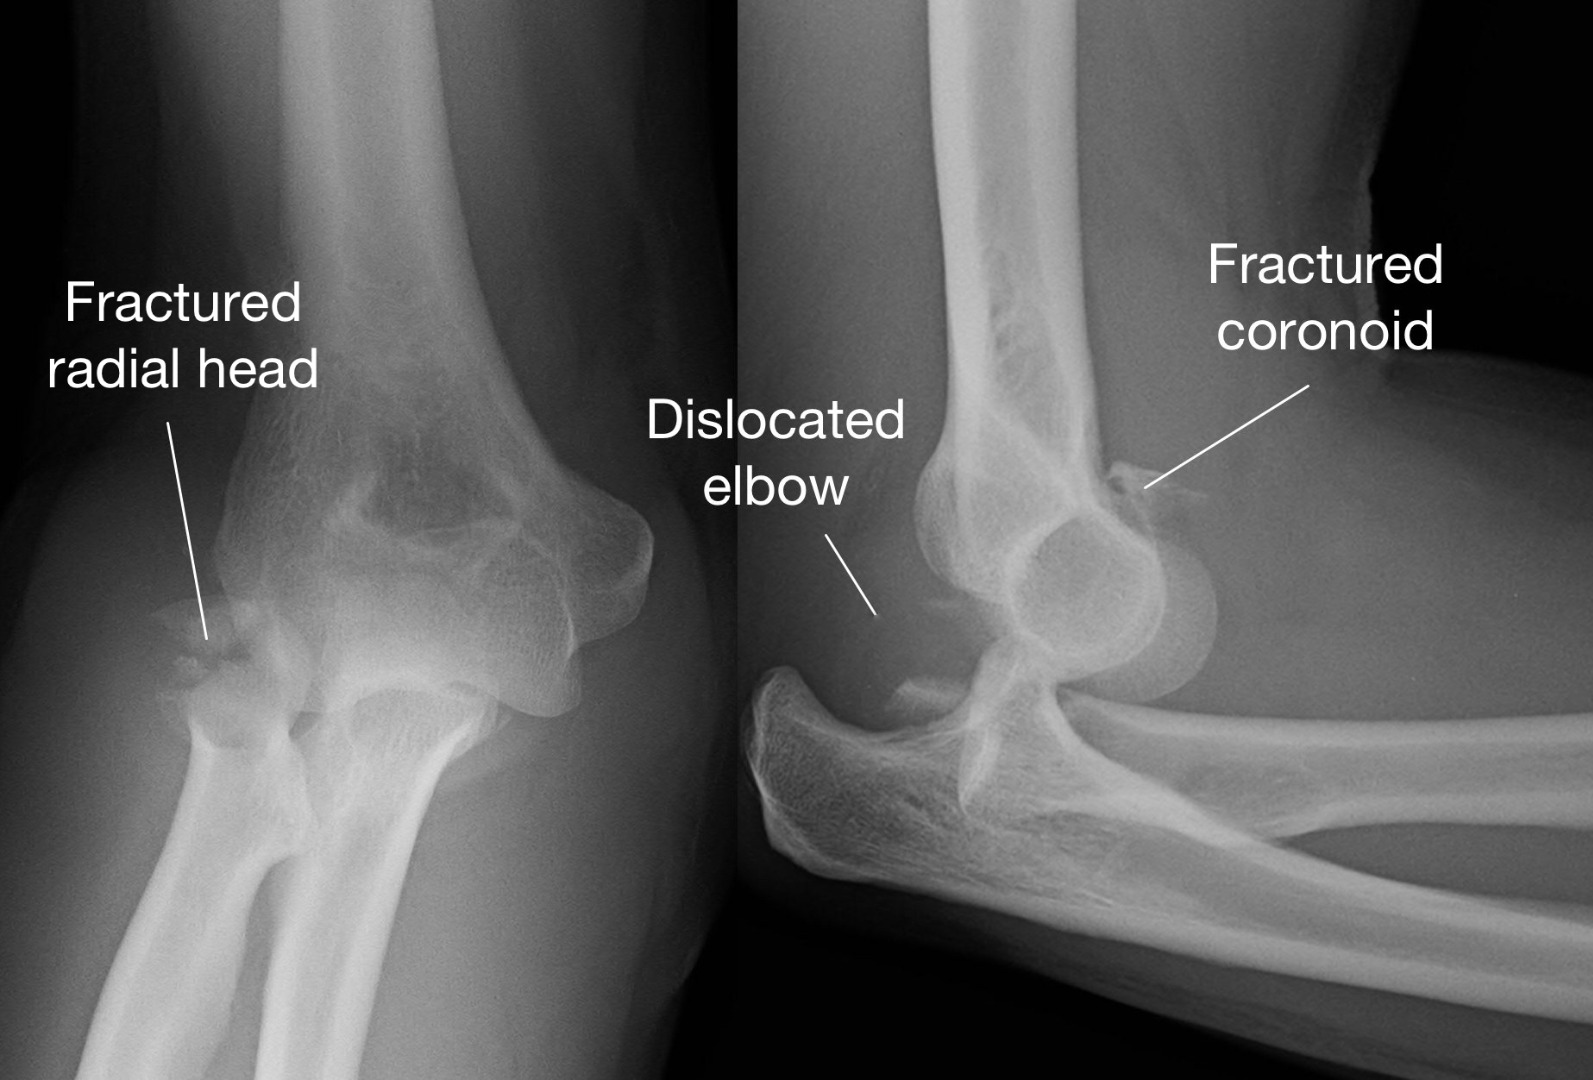

Understand the definition of a fracture and types of bone breaks, including compound, simple, and stress fractures. Learn how these musculoskeletal injuries occur, the common symptoms to watch for, and the essential medical treatments required for proper healing. Explore our comprehensive guide to bone health and emergency orthopedic care for improved recovery outcomes.